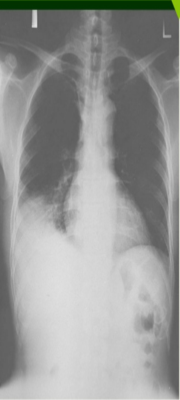

Mujer de 46 años sin antecedentes patológicos relevantes. No tiene alergia a medicamentos. Fumadora de 10 cigarros por día. Desde una semana antes de su ingreso comienza con fiebre de hasta 38º C y dolor torácico retroesternal de carácter punzante, que aumenta con la tos pero no con los movimientos y que cede con ibuprofeno. No expectoración. Pruebas complementarias: ECG: ritmo sinusal a 100 lats/min Hemograma: Leucocitos 15.39 10E3/µL, (N 89.3 %, L 4.4 %, M 4.5 %, Eo 0.7 %, B 0.2 %), Hb 11.4 g/dL, Hcto. 33.1 %, VCM 77.8 fL, Plaquetas 428 10E3/µL. Coagulación y bioquímica sin alteraciones relevantes. CPK y troponina Ic normales. La radiografía de tórax de la paciente se muestra en la figura 1. En ella lo más llamativo es la presencia de una discreta cardiomegalia. Se presenta radiografía. ¿Cuál es su diagnóstico?

Answer

• Derrame pericárdico, es la presencia de líquido en la cavidad pericárdica o derrame pericárdico apreciandose una imagen del corazón en forma de "botella“ en la Rx.

• Tamponamiento Cardíaco como como consecuencia de la acumulación de líquido a tensión, lo que anula el efecto de la presión negativa intratorácica sobre el llenado cardíaco y ofrece una resistencia a la expansión ventricular durante el llenado diastólico.

• Pericarditis aguda idiopática, en la segunda radiografía aplicada se aprecia además de la cardiomegalia datos sugerentes de derrame pleural bilateral.